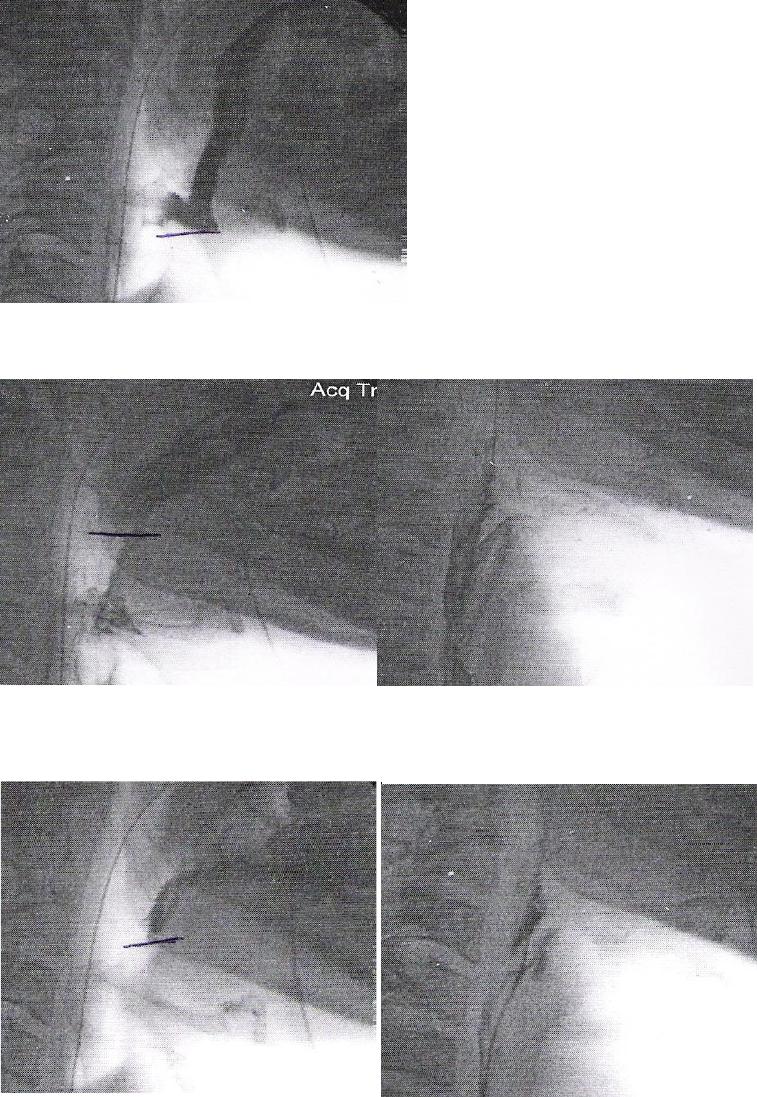

ANEXO E Imagens videofluoroscópicas da deglutição, registrando

escape prematuro e reação de deglutição atrasada, p e s

crioestimulação, com líquido e pastoso.........................................................